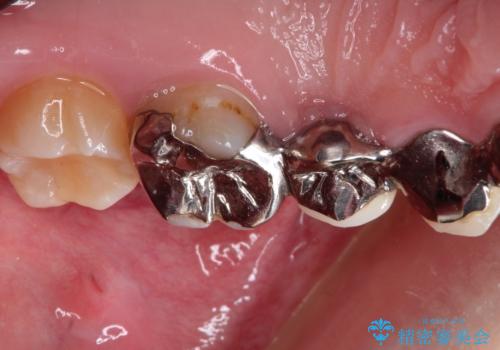

また奥歯にまたがるブリッジも金属のもので、適合もよくありませんでした。

オールセラミックによるやりかえを行いました。